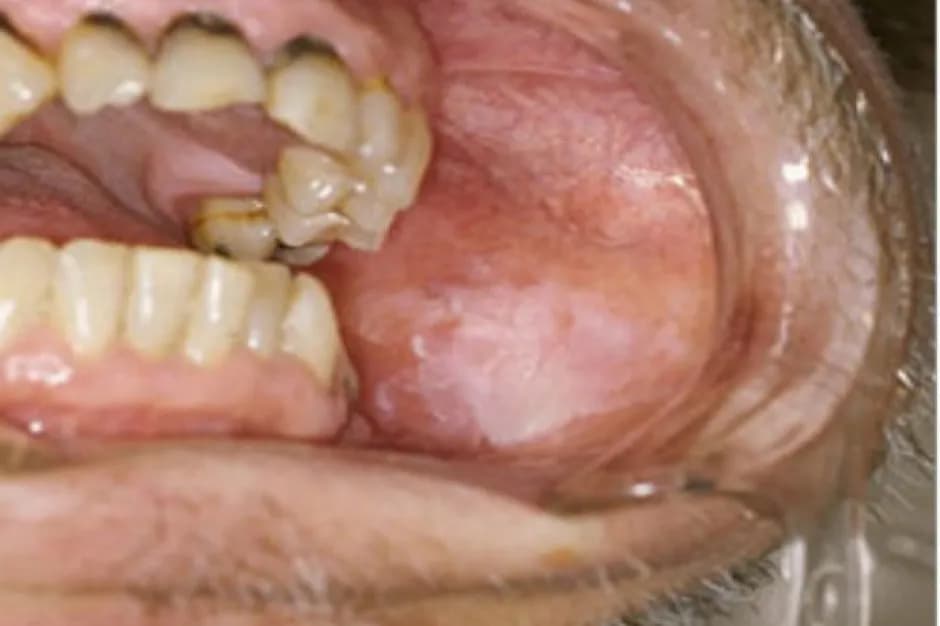

Zmiany kolorystyczne w obrębie dziąseł mogą być jednym z pierwszych sygnałów, że coś jest nie tak. Różne odcienie czerwieni, bieli lub ciemnych plam mogą wskazywać na obecność raka dziąseł. Zmiana koloru dziąseł na intensywną czerwień może sugerować stan zapalny, ale także być oznaką nowotworu. Z kolei białe plamki, znane jako leukoplakia, mogą być wczesnym objawem raka i powinny być dokładnie zbadane przez specjalistę.

W przypadku wystąpienia ciemnych plam na dziąsłach, warto skonsultować się z dentystą, ponieważ mogą one być oznaką zaawansowanego procesu chorobowego. Szybka reakcja na te zmiany może znacząco zwiększyć szanse na wczesne wykrycie i skuteczne leczenie. Dlatego tak ważne jest, aby regularnie monitorować stan zdrowia jamy ustnej i zwracać uwagę na wszelkie niepokojące zmiany kolorystyczne.